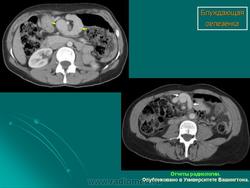

Селезёнки патология. Пнд, 09/09/2013 - 22:59 #1 Катенёв Валенти... Не на сайте Был на сайте: 7 лет 4 месяцев назад Зарегистрирован: 22.03.2008 - 22:15 Публикации: 54876 Спленомегалия Figure 46: Splenomegaly, contrast enhanced CT Пнд, 09/09/2013 - 23:00 #2 Катенёв Валенти... Не на сайте Был на сайте: 7 лет 4 месяцев назад Зарегистрирован: 22.03.2008 - 22:15 Публикации: 54876 Киста селезенки Figure 48: Spleen cyst, contrast enhanced CT Пнд, 23/09/2013 - 21:48 #3 Катенёв Валенти... Не на сайте Был на сайте: 7 лет 4 месяцев назад Зарегистрирован: 22.03.2008 - 22:15 Публикации: 54876 Полиспления ID: 18841 Polysplenia syndrome Dr Ian Bickle - 24 Jul 2012 Features of polysplenia syndrome (aka left sidedness or left isomerism) ... ID: 12761 Polysplenia syndrome , situs ambiguous, rectal mass Dr Amro Nazih Omar - 7 Jan 2011 Axial CECT demonstrates polysplenia, situs ambiguous, absent IVC an... Случаи и цифры Дело 1 Случай 2: Случай 3: Случай 4 Случай 5: situs inversus abdominalis